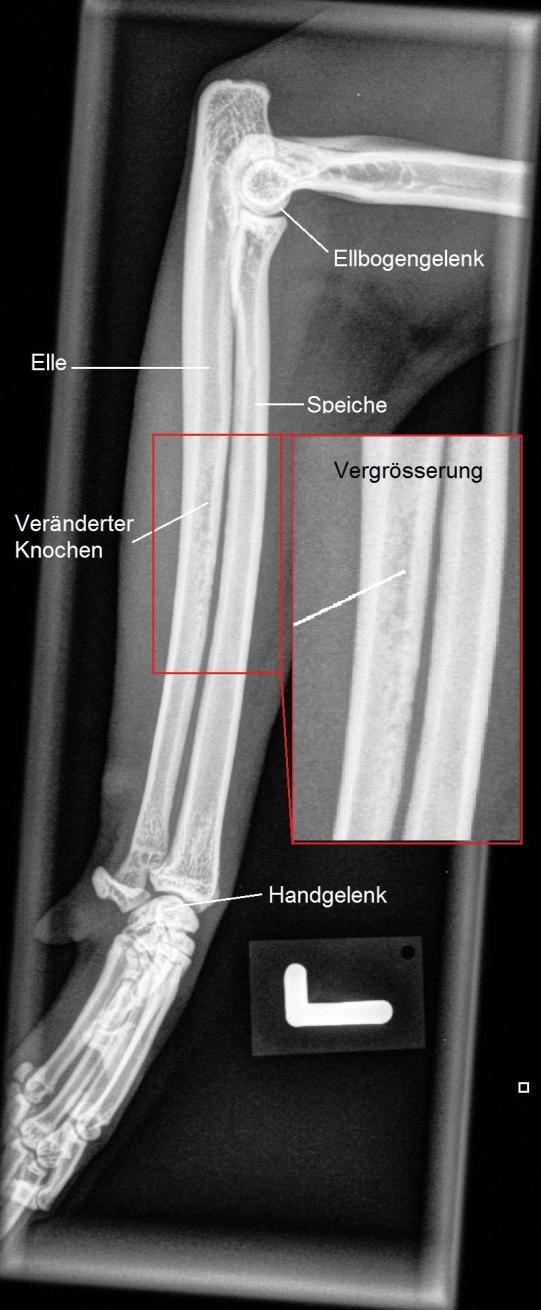

Leider erfüllt sich die Hoffnung, dass es sich nur um eine harmlose Verstauchung handelt, nicht - eine Woche später lahmt Barolo immer noch. Nun kann aber festgestellt werden, dass die Katze im mittleren Bereich des Unterarms schmerzhaft ist, weshalb die Region geröntgt wird: Die Elle ist in diesem Bereich fleckig verändert, was auf eine beginnende Auflösung des Knochens hinzuweisen scheint. Es ist zu befürchten, dass es sich um einen Knocheninfekt handelt, welcher sich Barolo bei einem Kampf zugezogen hat. Alternativ käme noch ein Befall mit Knochenkrebs in Frage, was aufgrund des Alters des Katers doch sehr unwahrscheinlich erscheint.

Zwei Wochen später hat sich die Schmerzhaftigkeit nur unwesentlich verbessert; im Röntgen erscheint die Veränderung trotz Antibiotikum sogar eher verstärkt. Könnte es tatsächlich sein, dass es sich um Knochenkrebs handelt? In diesem Fall müsste die Diagnose mittels Knochenbiopsie gestellt werden und im schlimmsten Fall das Bein amputiert werden. Vorerst entscheiden wir uns aber, die Antibiotikumtherapie um ein zweites Präparat aufzustocken und so die Behandlung zu intensivieren.

Zwei weitere Wochen später können wir endlich aufatmen und das Bein wird erneut geröntgt. Barolo geht es nun viel besser, er zeigt keine Schmerzen mehr, und auch die Röntgenaufnahme zeigt, dass sich die Veränderungen langsam zurückzubilden scheinen. Ganz offensichtlich hat es sich hier tatsächlich um einen (wohl durch einen Katzenbiss verursachten) bakteriellen Infekt der Elle gehandelt.